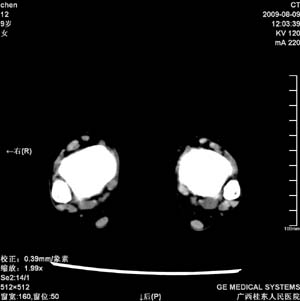

标题: PED2867:右侧内踝肿胀,骨质改变,请各位老师会诊 [打印本页]

标题: PED2867:右侧内踝肿胀,骨质改变,请各位老师会诊

九岁小朋友,近期左侧内踝疼痛,局部肿胀,平时无特殊,近期经常溜干冰

对不起,是右侧内踝肿胀

双踝关节骨质及发育未见异常。

左侧内踝密度增高,请结合临床!

双侧踝关节骨质及关节结构均未见明显异常。考虑玩多了累的,休息休息看看吧!